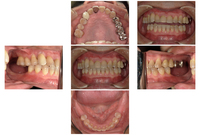

全体的に虫歯ができてしまっていた方の治療報告をさせて頂きます。

50代の男性の患者さんです。

虫歯のよりかみ合わせが崩壊してしまっています。

保存できない歯も多数ありました。

術前